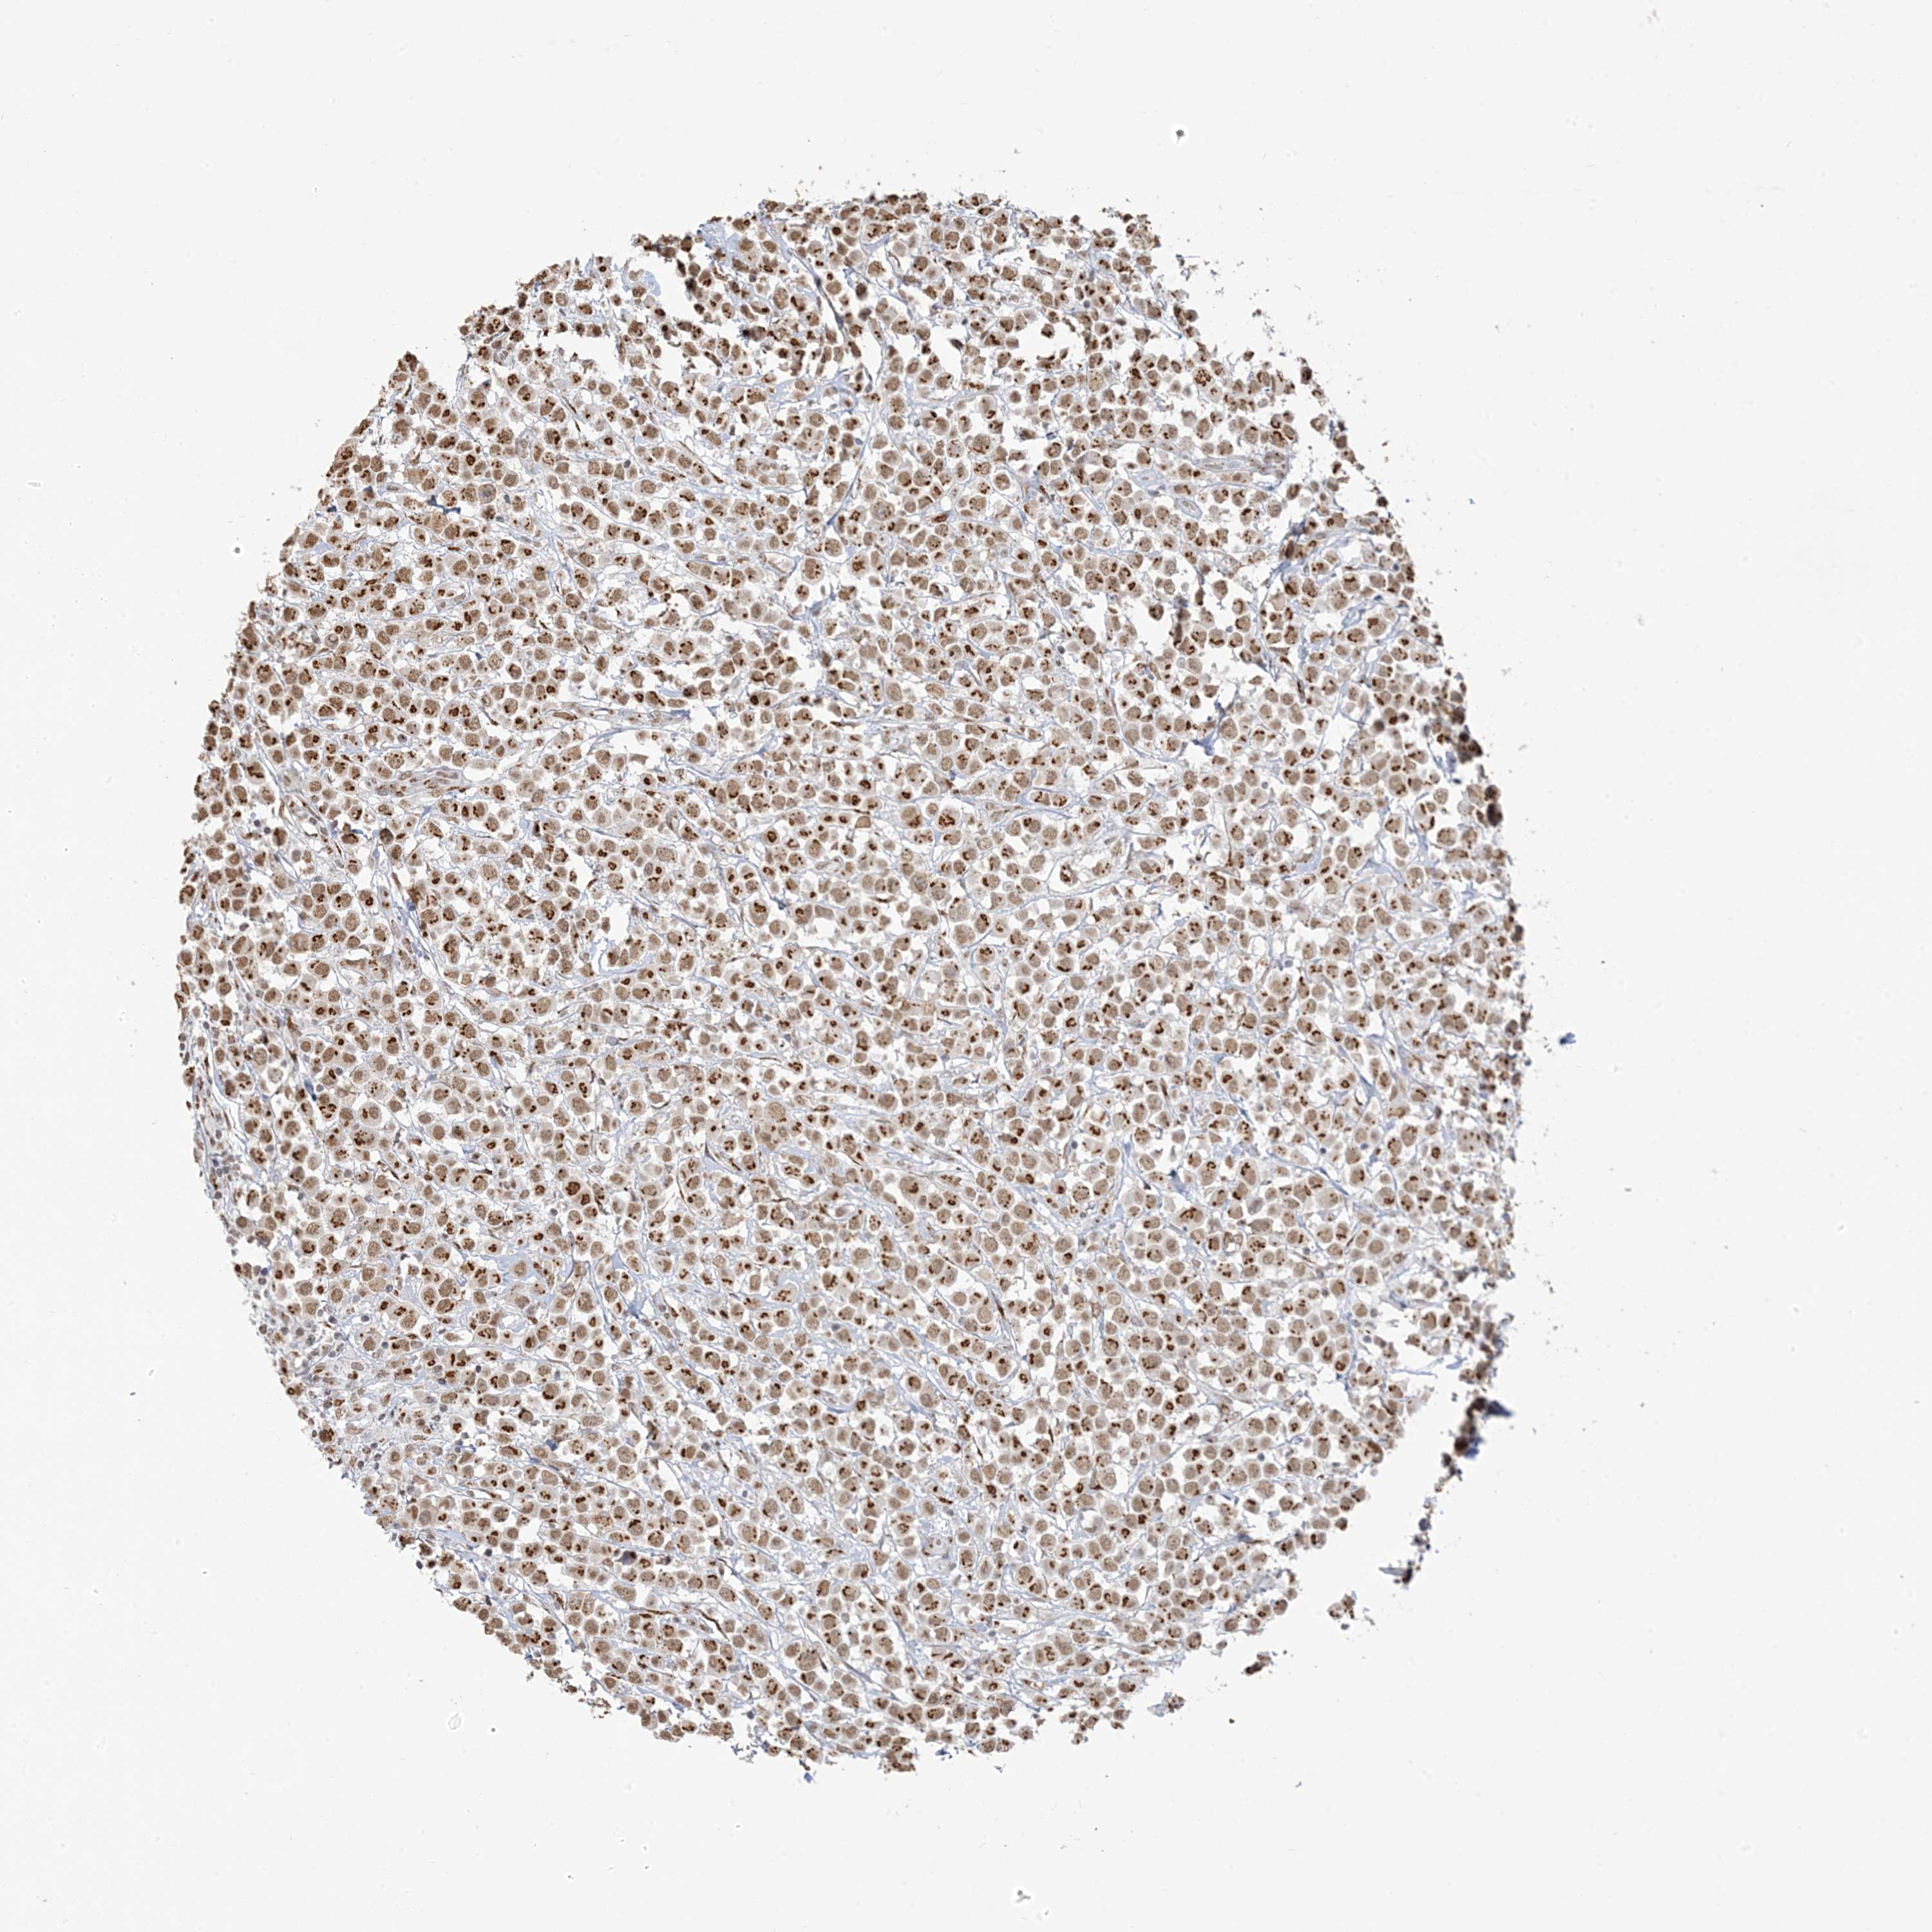

CANCER BREAST CANCER Show tissue menu

BRCA TCGA BRCA VALIDATION PROTEIN EXPRESSION